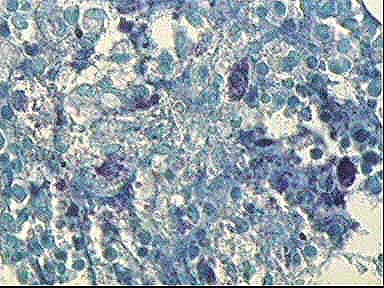

Figura 15.. Azul de Toluidina x400

figura 16

Figura 16.. Azul de Toluidina x400

figura 17

Figura 17.. Azul de Toluidina x630

figura 18

Figura 18.. Azul de Toluidina x630

figura 19

Figura 19.. Giemsa x200

figura 20

Figura 20.. Giemsa x400